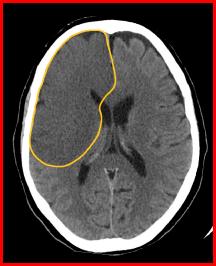

The primary treatment for nonhemorrhagic strokes is the administration of thrombolytics (e.g. tissue plasminogen activator, t-PA) prior to the development of ischemic necrosis. Since thrombolytics would exacerbate hemorrhagic bleeds, the distinction between hemorrhagic and nonhemorrhagic strokes is critical. Fortunately, as you can see, the distinction is quite apparent on a non-contrast CT scan.

Non-contrast CT is a critical component for the evaluation and subsequent treatment of strokes.

When examining these CTs, remember that collections of blood will be radiodense. Initially infarcted brain will show minimal changes on a CT, but after a few days, there is marked effacement of the normal architecture.

Can you distinguish between these CTs and assign them each to one of the aforementioned categories?